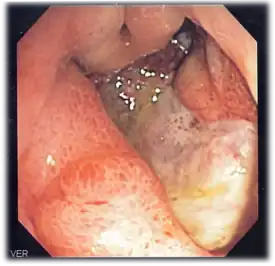

Endoscopic image of adenocarcinoma of duodenum seen in the post-bulbar duodenum.